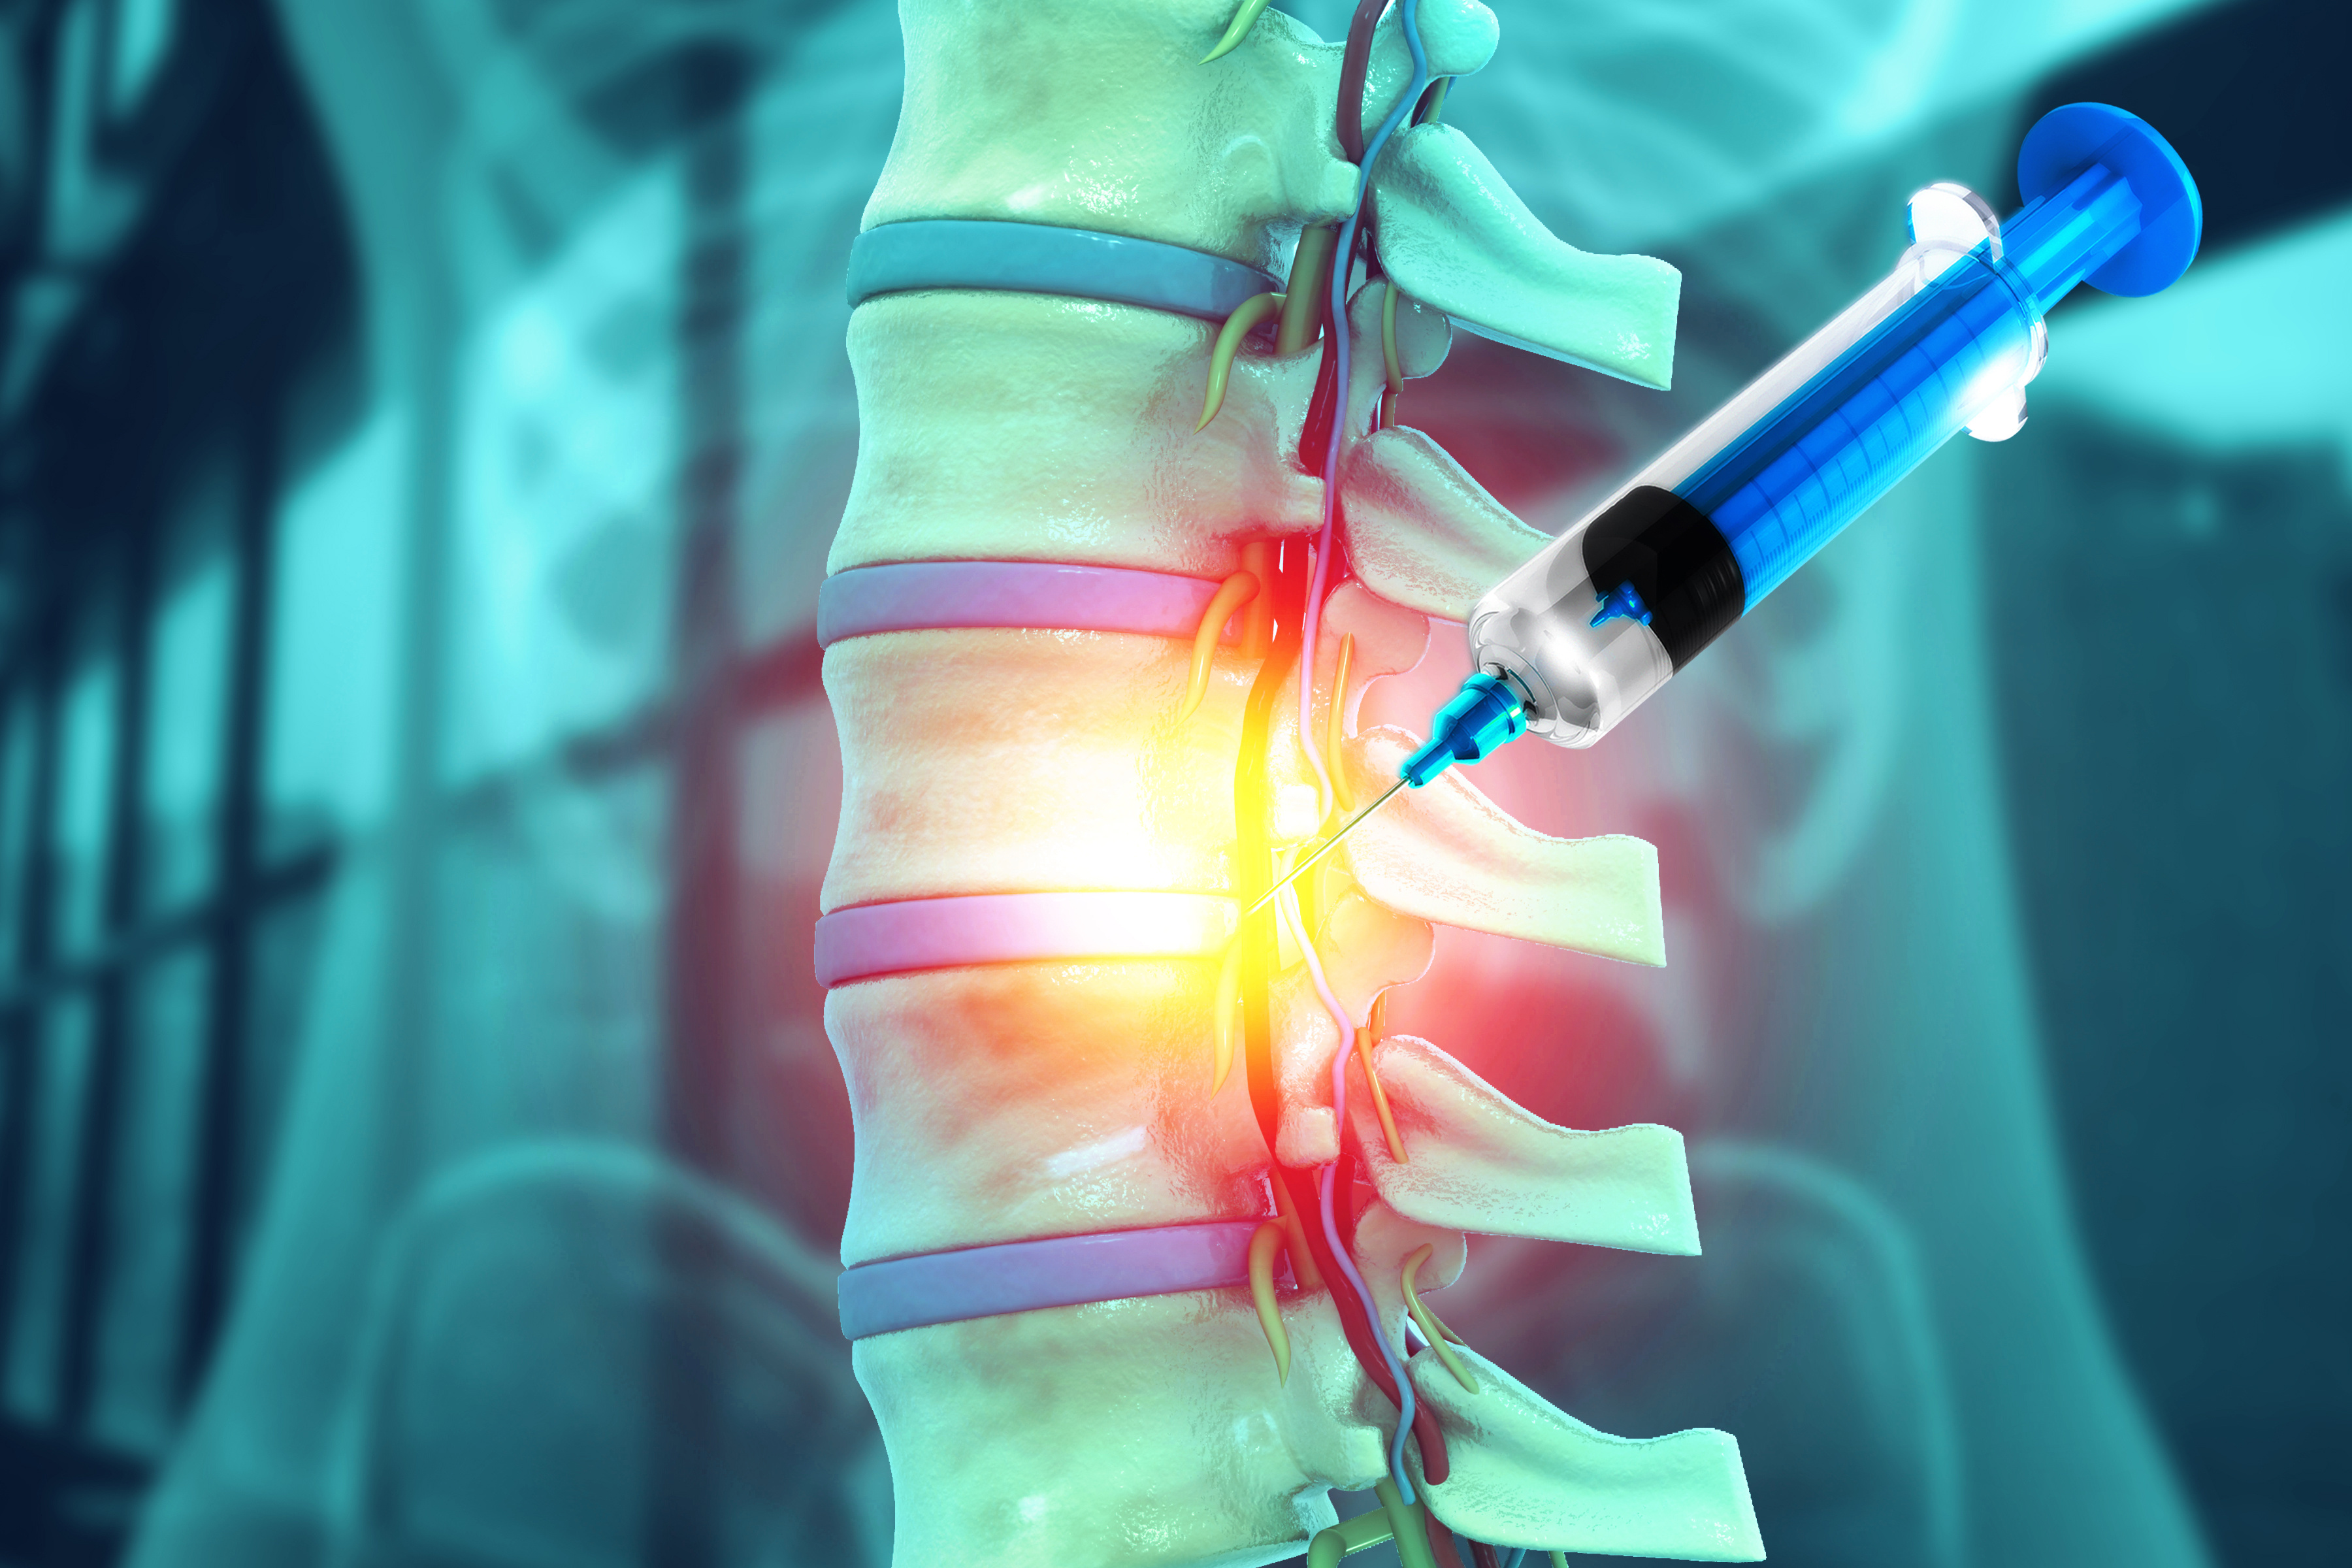

Las agencias nacionales de vigilancia sanitaria y control farmacéutico del MERCOSUR han puesto en marcha una masiva...

El Fondo para la Convergencia Estructural del MERCOSUR (FOCEM) ha ratificado la aprobación formal de un millonario...

La práctica médica está viviendo su mayor transformación desde la invención de los rayos X. Sin embargo,...